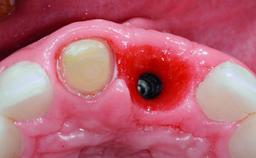

Replacement of a Compromised Upper Right Central Incisor: Hard- and Soft-tissue Augmentation, Late Placement of an RC Bone Level Implant

A 36-year-old male patient with a compromised maxillary central incisor was referred by his general dentist for consultation. The patient’s chief complaints were the gradual debonding of a temporary crown on the right central incisor and unsatisfactory esthetics due to an increasing diastema between the right central and lateral incisors. The patient reported a traumatic event some years previously, when a crown had been placed after root-canal treatment. The referring dentist wanted to provide a new crown restoration, but was concerned about the condition of the residual root. Anamnesis was negative for any other dental or periodontal pathology in the remaining dentition. The patient reported taking no medications: He was a smoker (10 to 15 cigs/day) and had realistic esthetic expectations.

Bone Augmentation Horizontal|Simultaneous|Staged

Augmentation Materials Xenogenous|Membrane

Soft Tissue Grafting Simultaneous

Bone Volume Deficient horizontally, requiring prior grafting